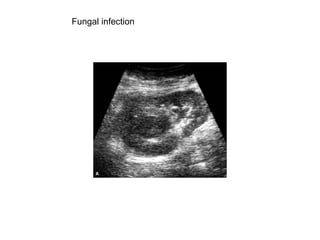

Fungal infection

Typical fungal balls are seen in the bladder

Another case with fungal balls in the renal collecting system.